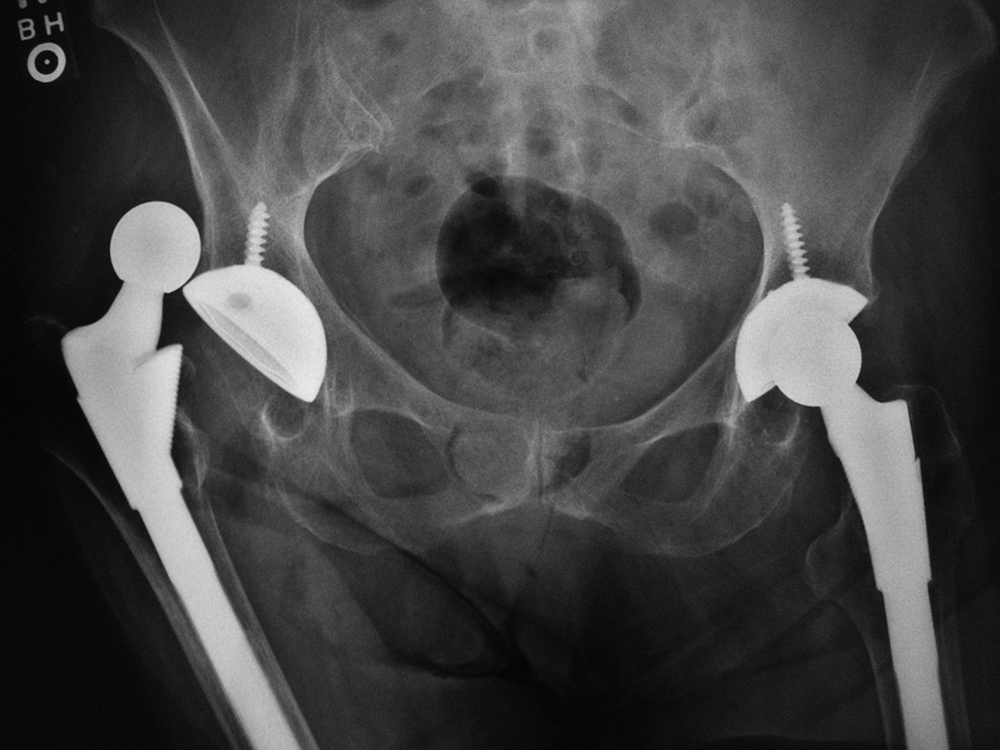

Bilateral total hip arthroplasty (THA) |

38 year old man with bilateral THA for advanced osteoarthritis. |

| Bilateral total hip arthroplasty (THA) |

| 38 year old man with bilateral THA for advanced osteoarthritis. The acetabular cup on an AP view of the pelvis should have 30-50 degrees of lateral inclination, which is measured as the angle between the rim of the acetabular cup and a line tangential to the ischial tuberosities. |

38 year old man with bilateral THA for advanced osteoarthritis. The distances from a line (C) between the centers of the femoral heads to a line running tangential to the ischial tuberosities (A) should be equal on each side, and the distances between the centers of the femoral heads to a line (B) running tangential to the tops of the greater trochanters should be equal on each side. Lines A, B, C should be parallel. |

38 year old man with bilateral THA for advanced osteoarthritis. The distances from the centers of the femoral heads on each side to the tops of the acetabular tear drops should be equal. |